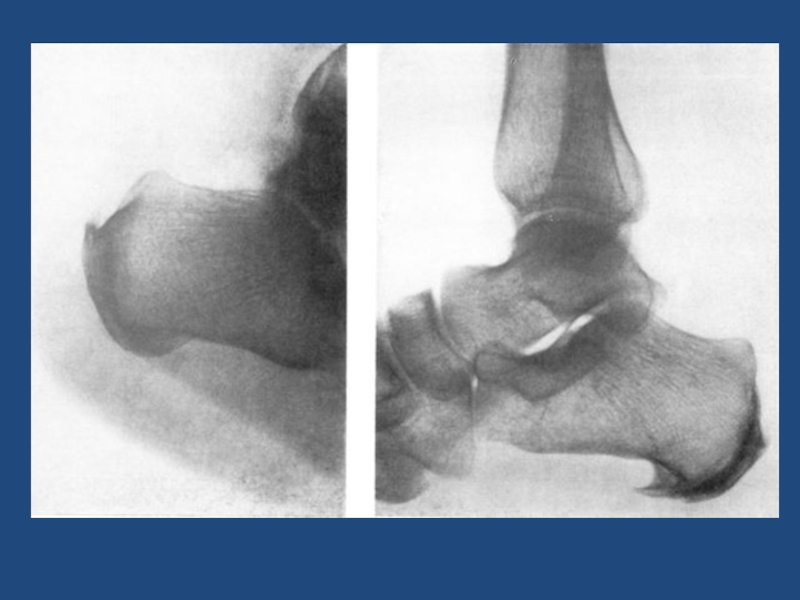

Разрыв наружной боковой связки справа